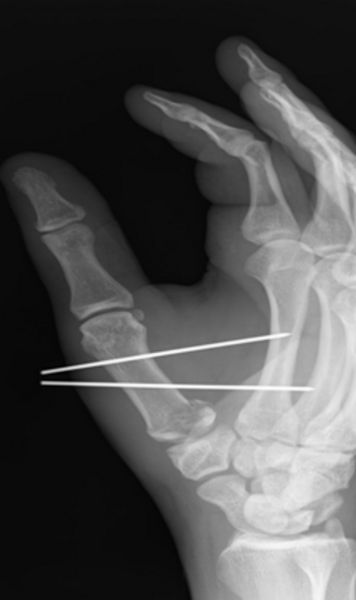

Die operative Versorgung der Metacarpale V Frakturen erfolgt entweder in der Regel mit Drähten, gelegentlich ist der Einsatz einer Plattenosteosynthese (Verplattung) notwendig.

Bei Metacarpale I Frakturen müssen Bennett – und Rolandofrakturen immer operativ versorgt werden, hier wird der Operateur entscheiden, ob eine Spickdrahtversorgung oder eine Plattenosteosynthese erfolgt.